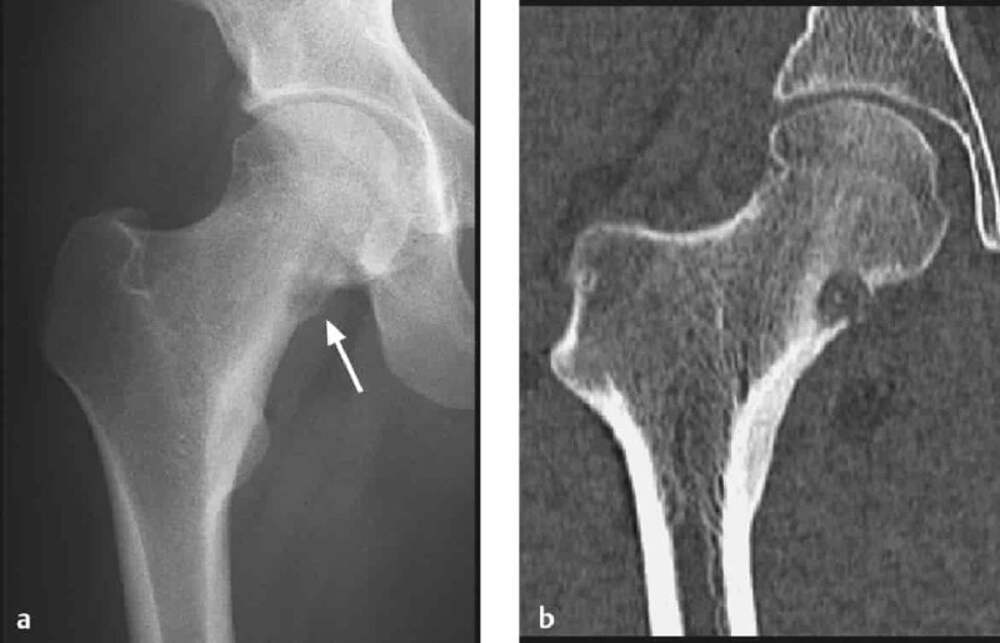

Остеоид-остеома

Доброкачественная опухоль остеогенной природы. Наблюдается в возрасте от 5 до 25 лет. Опухоль локализуется в компактном слое диафиза бедренной или большеберцовой костей. Чаще поражает кости нижней конечности, но может также поражать тела позвонков и ребра. Процесс, как правило,